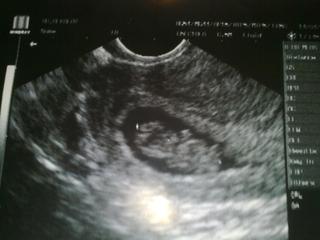

Na UTZ vse v poradku,srdicko ~s~ bilo jako zvon, miminko odpovida tydnu a vse je v poradku.

Mimi ma kolem 3cm

eme: to je krásný 😀 😀 je tam fazolka už pěkně vidět....já nic takovýho z těhu nemám, dr. měla ještě starý UTZ a tam to nebylo moc vidět, sice jsem fotečku dostala, ale nic moc tam vidět není